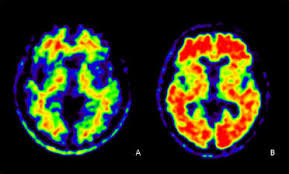

La Scintigraphie est un examen fonctionnelle mais aussi une technique d'imagerie qui en médecine nucléaire permet d'explorer la forme et le fonctionnement des tous les organes, de voir la présence de tumeur primaire ou secondaire et l'origine de douleurs ou de la maladie. Elle peut servir à confirmer un diagnostic incertain.

Scintigraphie de la thyroïde